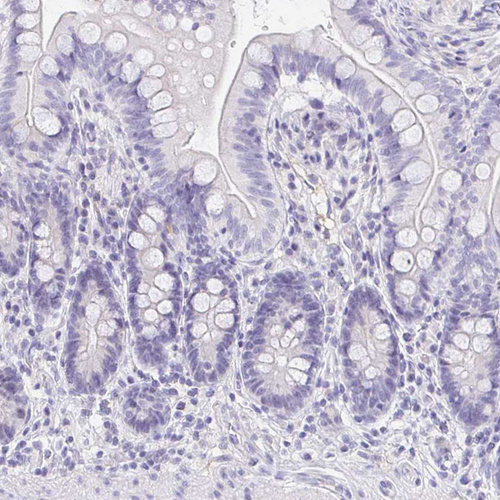

Immunohistochemistry analysis in human testis and prostate tissues using HPA015504 antibody. Corresponding EQTN RNA-seq data are presented for the same tissues.